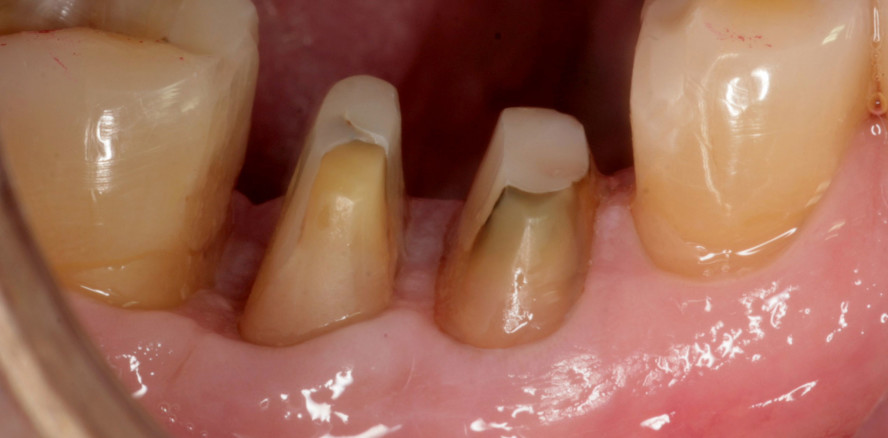

Eine anatomische Besonderheit von mehrwurzeligen Zähnen stellt der Bereich der Wurzelteilungsstelle (Furkation) dar, die aufgrund ihrer individuellen und variantenreichen Form spezifische Herausforderungen für den Behandler mit sich bringt.2 Die Furkation ist charakterisiert durch Einziehun-gen der Wurzeln und die damit entstehenden Unterschnitte (Abb. 2).2 Diese Besonderheiten betreffen sowohl die konservative Therapie der Wurzelglättung als auch die resektive Parodontalchirurgie.

Die schmalen Furkationseingänge (Abb. 2) erschweren beim Scaling and Root Planing (SRP) die Instrumentierung des interradikulären Raumes. Diese anatomischen Merkmale sind auch im Rahmen der resektiven Parodontaltherapie von entscheidender Bedeutung, da sie in der chirurgischen Präparation berücksichtigt werden müssen, um ein optimales Behandlungsergebnis zu erzielen.